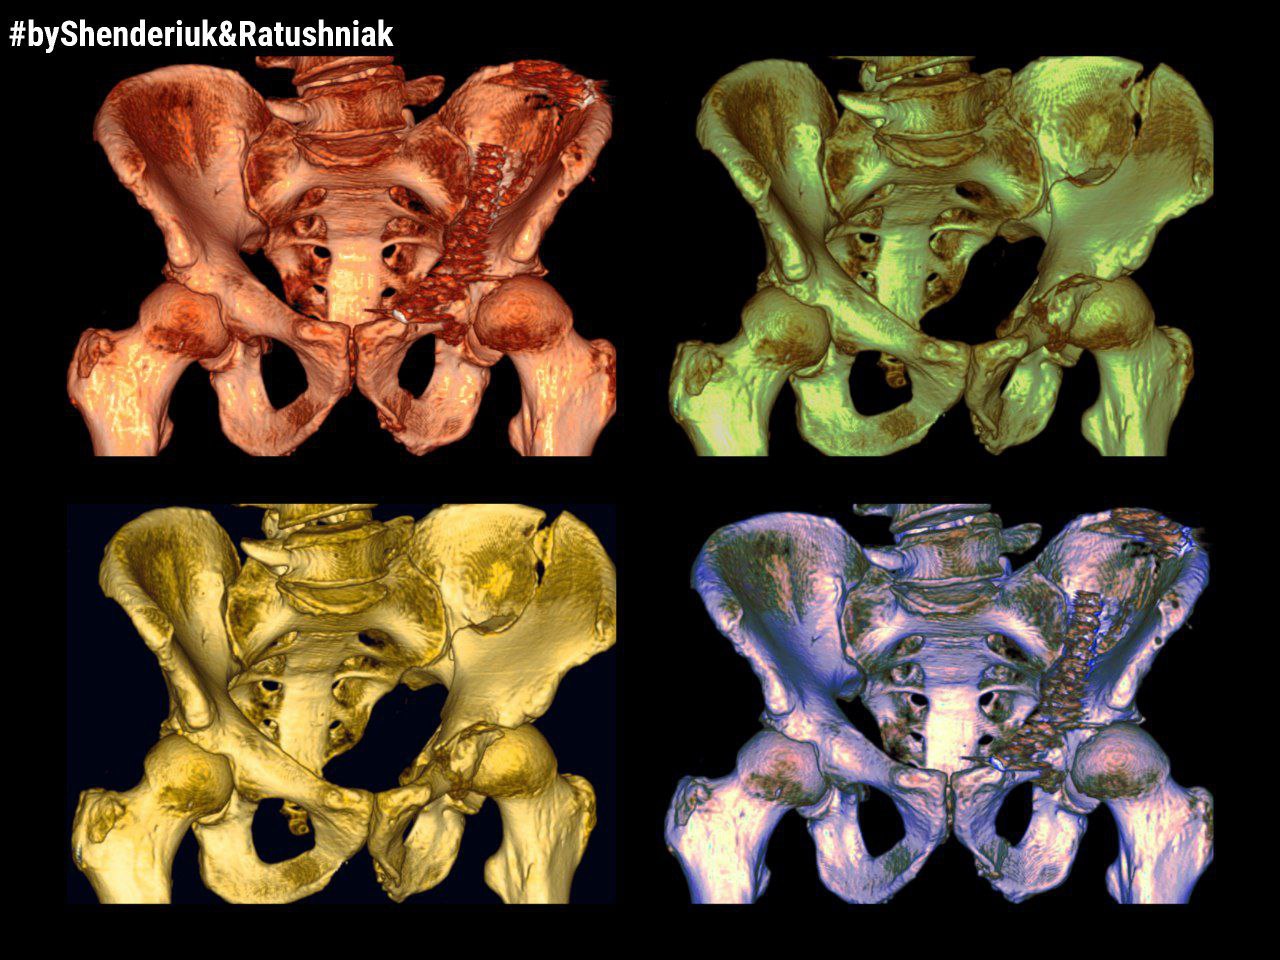

КОРОТКИЙ ЗВІТ ЩОДО ЛІКУВАННЯ ПЕРЕЛОМІВ ТАЗУ

Зима - це не лише свята. З її настанням скорочується довжина світлового дня та погіршуються погодні умови, дороги вкриваються ожеледицею,